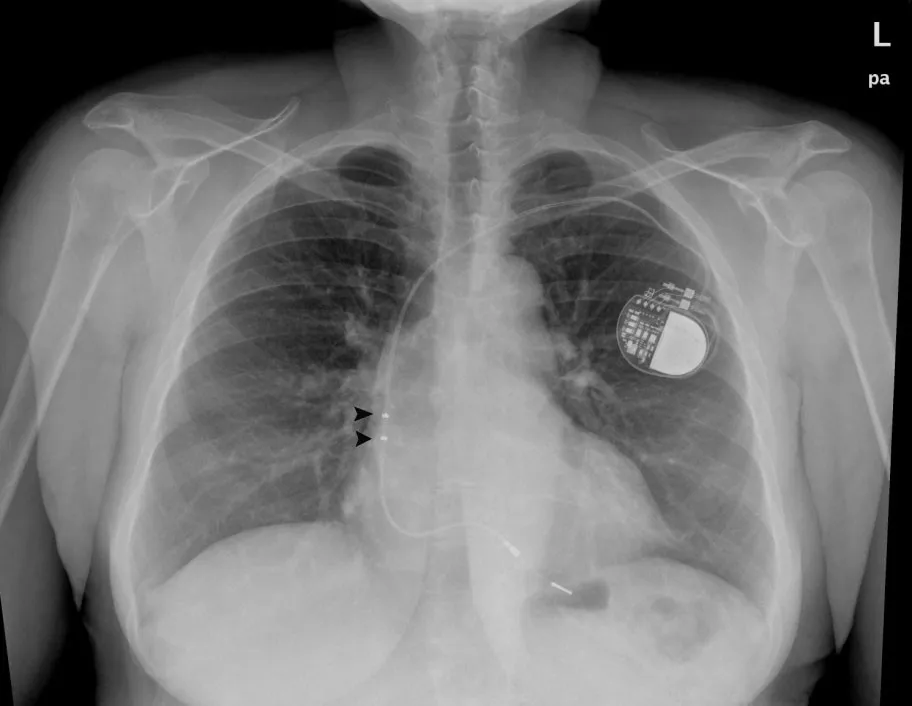

In samenwerking met de Stichting Pacemakerdragers Nederland organiseert Atrium-Orbis op vrijdag 17 april een bijeenkomst voor pacemakerdragers.

Cardioloog in Atrium-Orbis Heerlen Guido Paulussen vertelt op deze middag over de redenen voor een pacemaker implantatie. Manon Minten en Mariska van den Biggelaar (beiden pacemaker techniscussen in het ziekenhuis) gaan in op wat er gebeurt tijdens een pacemakercontrole. Pacemaker techniscus John Ritzen vertelt onder andere over veilige pacemakersystemen.